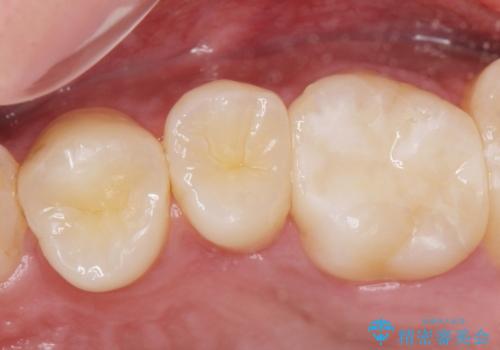

- 歯と歯の間に虫歯(コンタクトカリエス)が見られたので拡大鏡下で取り除き、e-maxインレーで治療を行いました。

- e-maxインレー 7.7万費用は治療当時の料金となります